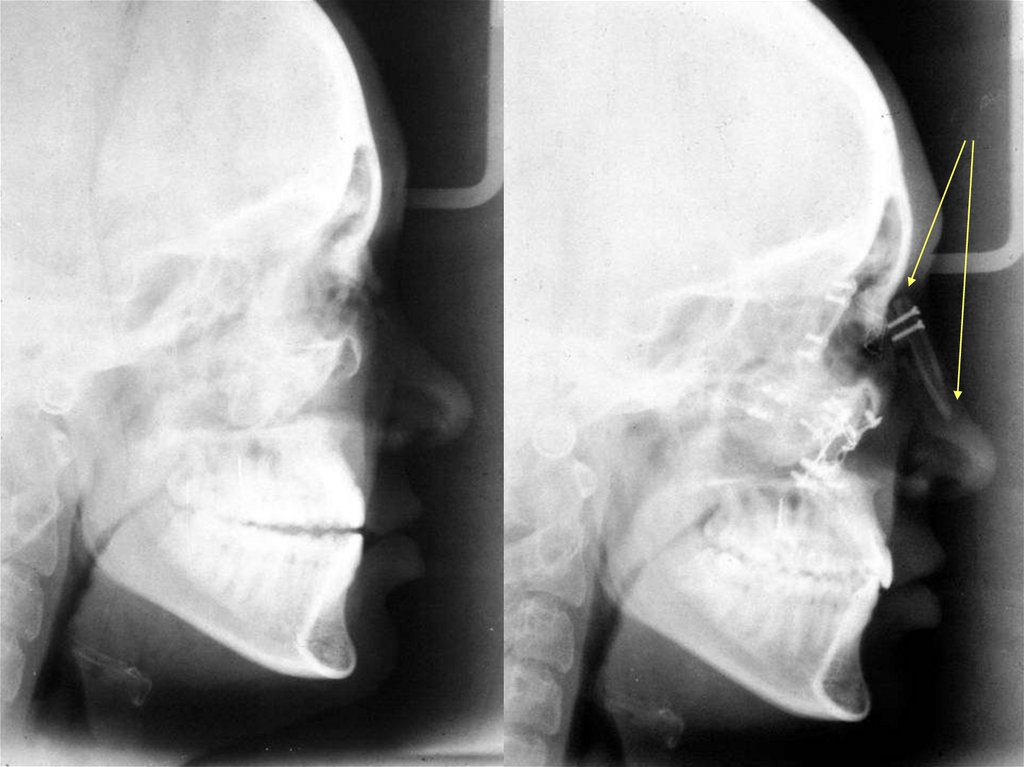

Схема взятия трансплантата из теменной

области